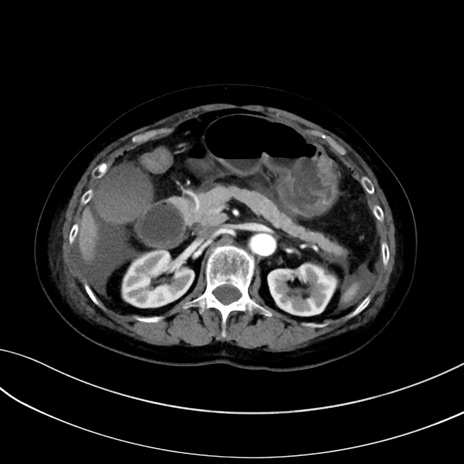

症例13 CT(横断像)1日半後